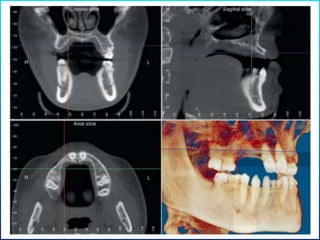

Available bone

It is the amount of bone in the edentulous area considered for implantation.

• Width

• Height

• Length

• Angulation

• Crown/implant ratio

Measured in :